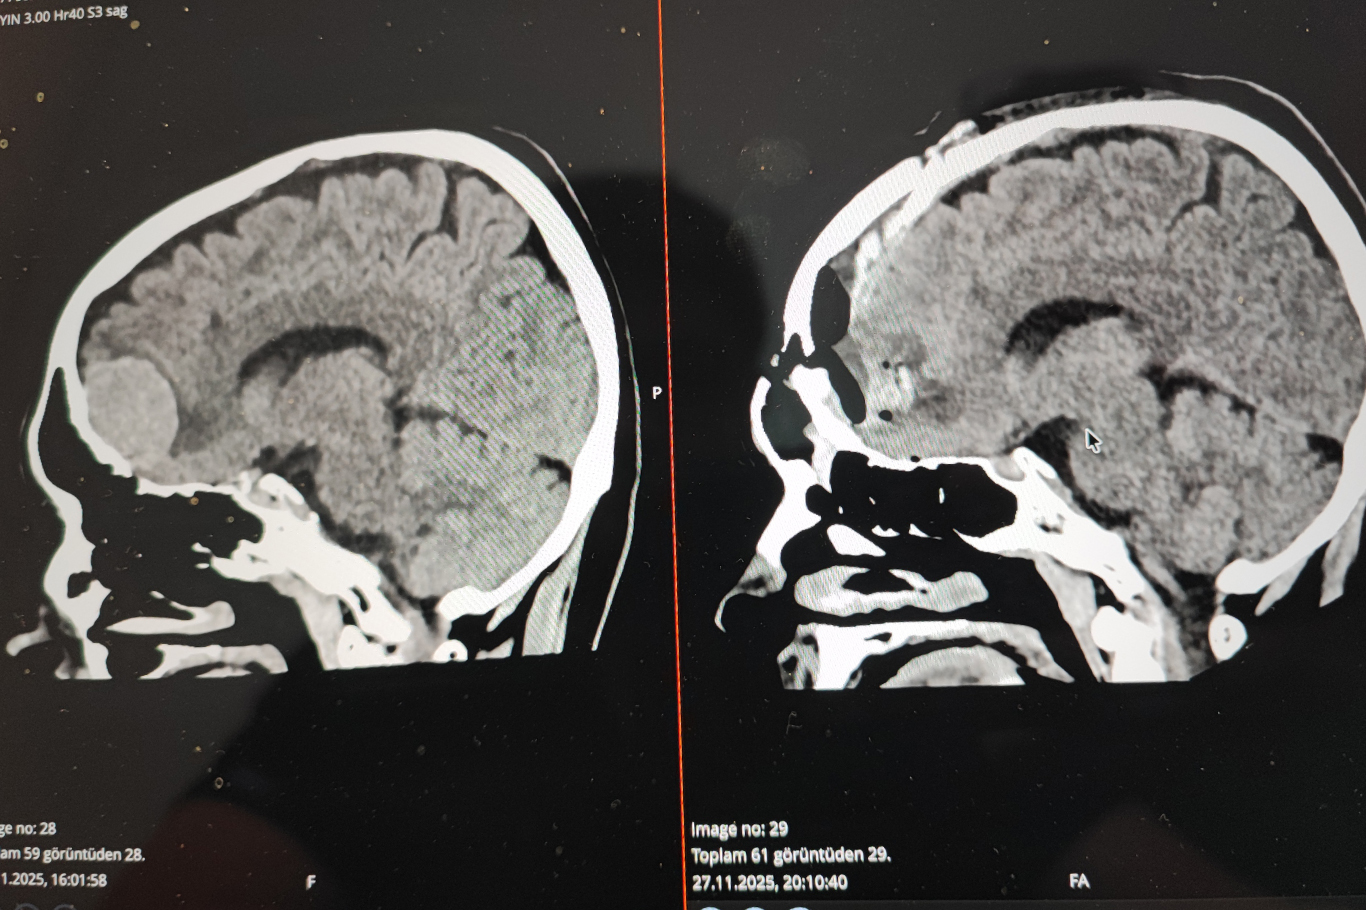

Teknolojinin hızla geliştiğini ve artık ameliyat süreçlerinde büyük kolaylık sağladığını vurgulayan Karatoprak, özellikle görüntüleme sistemlerinin önemine dikkat çekti.

Karatoprak, "Nöronavigasyon, monitörizasyon gibi yapay zekâ destekli görüntüleme sistemleri ameliyat sürecinde bize çok büyük destek sağlıyor. Geçmiş tetkikleri incelemek bazen saatler alırken yapay zekâ bunu dakikalar içinde analiz ederek önümüze getiriyor. Literatür taramaları, dünya çapındaki vaka incelemeleri çok kısa sürede yapılabiliyor." dedi.

Yapay zekânın tamamen bağımsız bir sistem değil, insanların ürettiği verilerle çalışan bir destek mekanizması olduğunu belirten Karatoprak, özellikle hız ve hata payını azaltma açısından büyük avantaj sağladığını ifade etti.